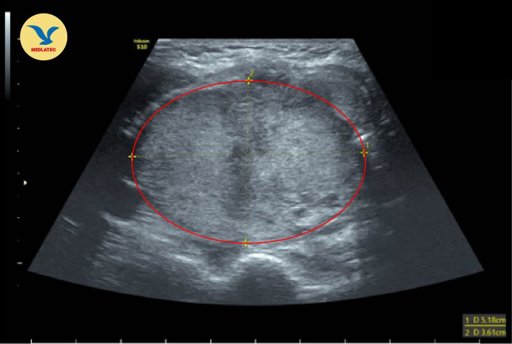

Phát hiện khối bất thường vùng cổ, đau nhẹ ngực trái - người phụ nữ được bác sĩ MEDLATEC chẩn đoán mắc ung thư biểu mô tuyến giáp thể nang giai đoạn IVB, hướng tới xâm lấn phần mềm, di căn hạch trung thất và phổi. Qua ca bệnh, bác sĩ khuyến cáo người dân, đặc biệt chị em phụ nữ không nên chủ quan...